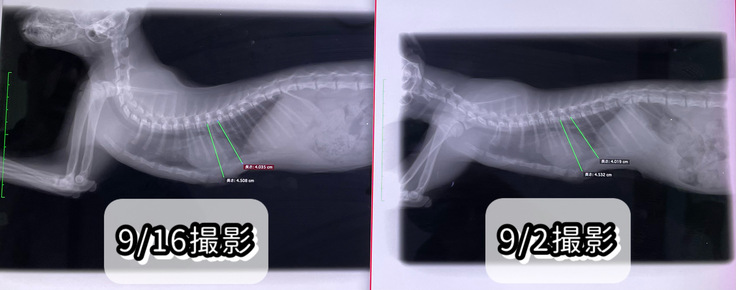

9/16(土)術後11回目の診察

本日は傷口の消毒とレントゲンを撮って

経過を診ていただきました。

傷口はかなり良くなって、次回の診察までにはほぼほぼ完治するだろう、とのことでした。

レントゲンも撮ってもらいましたが、

1〜2mmの戻りはありますが、

かなり良い感じ、とのことです!

体重も1.92kgになりました。

次回は2週間後に傷口を診てもらい、

さらに2週間後(1ヶ月後)にレントゲンを撮ってもらい

問題がなければ、一旦通院は終了となるそうです。